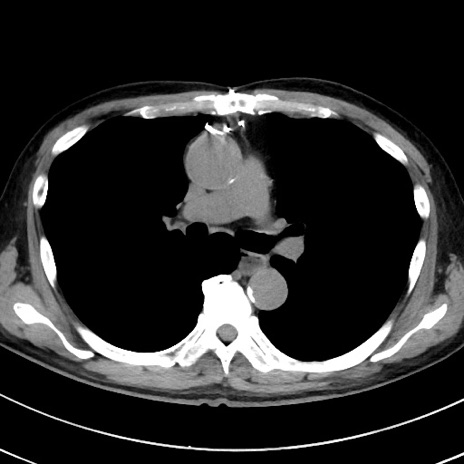

症例38(横断像)

【症例】70歳代 男性

【主訴】腹痛・嘔吐

【現病歴】昨晩より、嘔吐・腹痛あり。今朝になっても嘔吐あり。来院。

【既往歴】心臓バイパス手術、開腹胆摘、腸閉塞

【身体所見】BP 107/71mmHg、HR 116/min、腹部:平坦、軟、下腹部に軽度圧痛あり。反跳痛なし。

【データ】WBC 15100、CRP 0.32